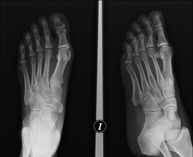

- RX Extremitats

Tècnica que usa els raigs X a través de la qual s'obtenen imatges de l'interior de les extremitats per al seu estudi, especialment dels ossos. Indicacions: traumatisme, infeccions articulars. - RX Artrografia

Tècnica que usa els raigs X a través de la qual s'obtenen imatges de la totalitat d'ambdues extremitats inferiors per al seu estudi, amb la valoració especialment de la presència de dismetries entre elles. - RX Extremitats

Tècnica que usa els raigs X a través de la qual s'obtenen imatges d'ambdues extremitats per al seu estudi. - RX Malucs